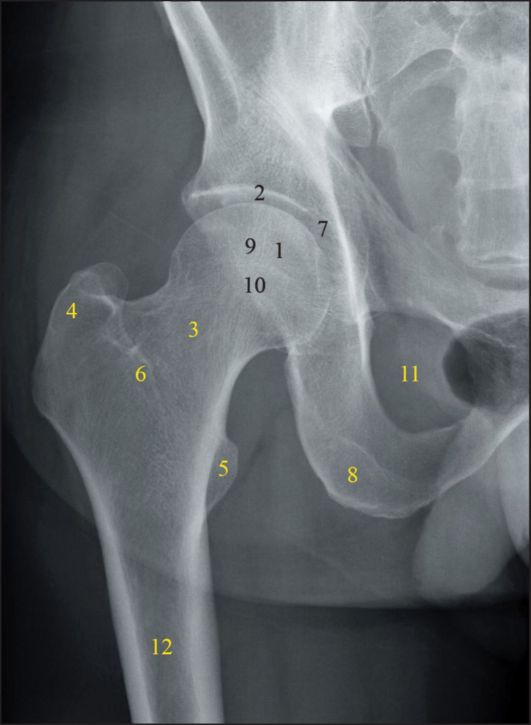

Рентген ТБС: Нормальные показатели

Раздел: Необычные решения